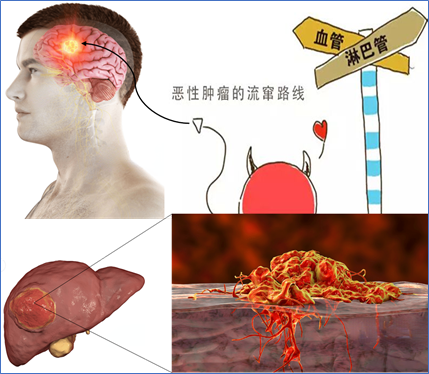

通俗来说:肝癌脑转移瘤的发生,一般是随着肝癌的进展,部分肿瘤细胞从肝癌原发病灶脱落,进入血液循环到达脑组织,其所流经血管直径越来越细窄,脱落的肿瘤细胞(团)可被“卡住”,逐渐在脑组织表面“安营扎寨”,形成新的肿瘤病灶,破坏正常脑组织,即发生脑转移。

肝癌脑转移发生途径